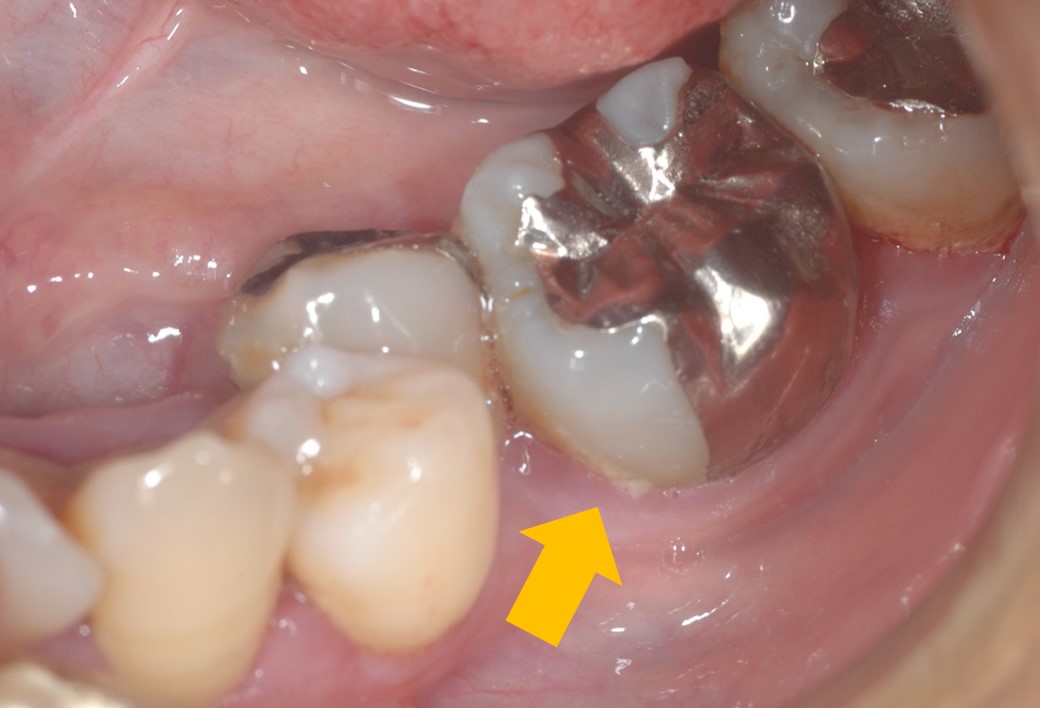

下写真をご覧ください。この矢印部分が「しみる」ようです。よく見ると、プラーク(白いもの=細菌の塊)が観察できます。このプラークは細菌であれば「酸」を代謝しますので、これが付いているだけでも「しみる」のです。